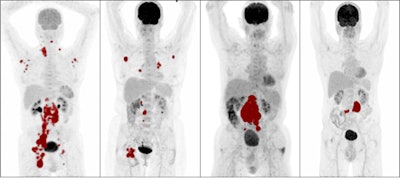

Dutch researchers pulled radiomics features -- standardized uptake values (SUV), dissemination features, and sphericity, or the measure of the roundness of tumors, for instance -- in patients with diffuse large B-cell lymphoma who had F-18 FDG PET scans. The group found the additional features significantly improved their ability to identify patients at high risk of relapse.

The researchers analyzed FDG PET/CT data from 317 newly diagnosed DLBCL patients who received baseline imaging at 58 hospitals as part of a phase III trial of a new monoclonal antibody treatment in 2020. Using a software program, they extracted 490 additional radiomics features from the PET scans, including simple features such as lesion SUV levels and the shape of tumors.

The researchers then developed six models based on combinations of IPI components and additional radiomics features, models including metabolic tumor volume (MTV), SUV levels, dissemination features, and sphericity. They then compared the models for predicting which DLBCL patients were likely to relapse after two years of first-line treatment.